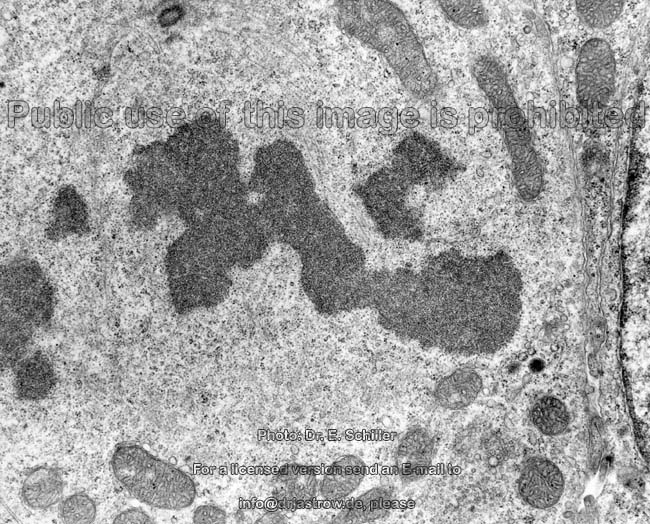

trinucleated cell of

Zona fasciculata (rat) |

central detail with saccular

mitochondria (rat) |